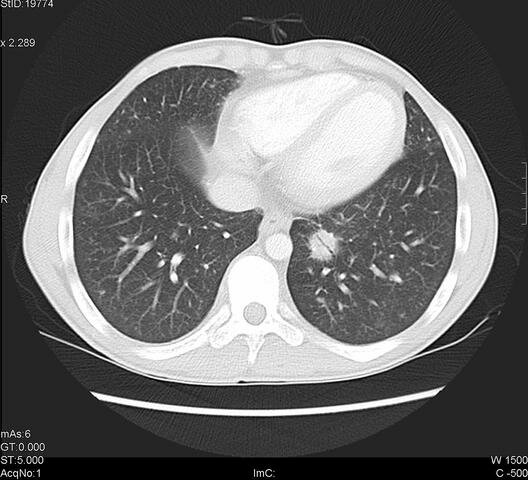

• Equipos helicoidales

Equipos helicoidales

Aparecen los equipos helicoidales con giros continuos y adquisiciones muy rápidas, realizando imágenes al rededor de 30 por segundo Se obtienen imágenes en 3D logrando ver imágenes instantáneas de diferentes planos como axial, coronal y oblicuos

Se utilizan medios de contraste